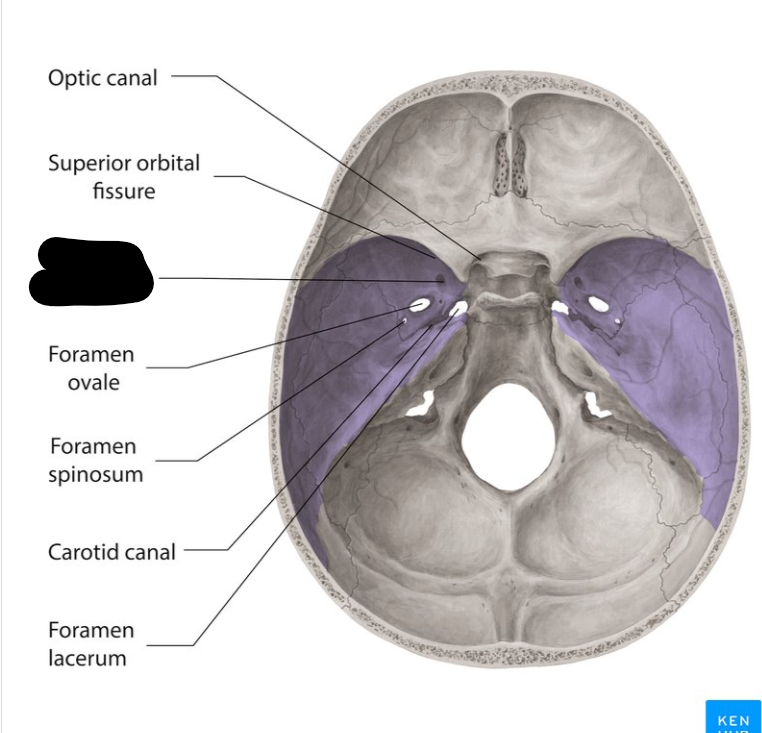

Middle cranial fossa

Foramen rotandum

Foramen ovale

Foramen lacerum

Foramen spinosum

Superior orbital fissure

Optic canal

Carotid canal